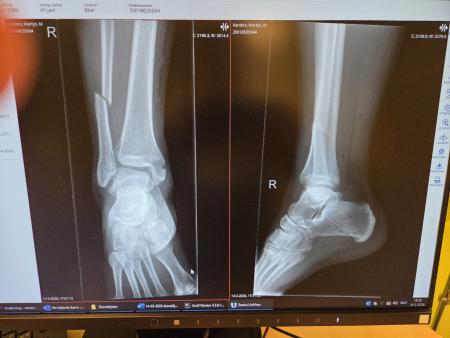

Enorme pech hebben Martijn Kanters en Rob de Vries gehad dit voorjaar. Beiden enkel gebroken. Rob kan inmiddels weer vooruit en op niet al te lange termijn Martijn ook. Dankzij hun directe collega's gaat het werk zo goed mogelijk door. TOP TEAM SPIRIT